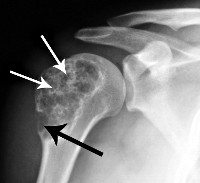

Для подтверждения диагноза делают рентгеновские снимки, магнитно-резонансную или компьютерную томографию, а чтобы убедиться в отсутствии метастазов - флюорографию или радиоизотопное сканирование.